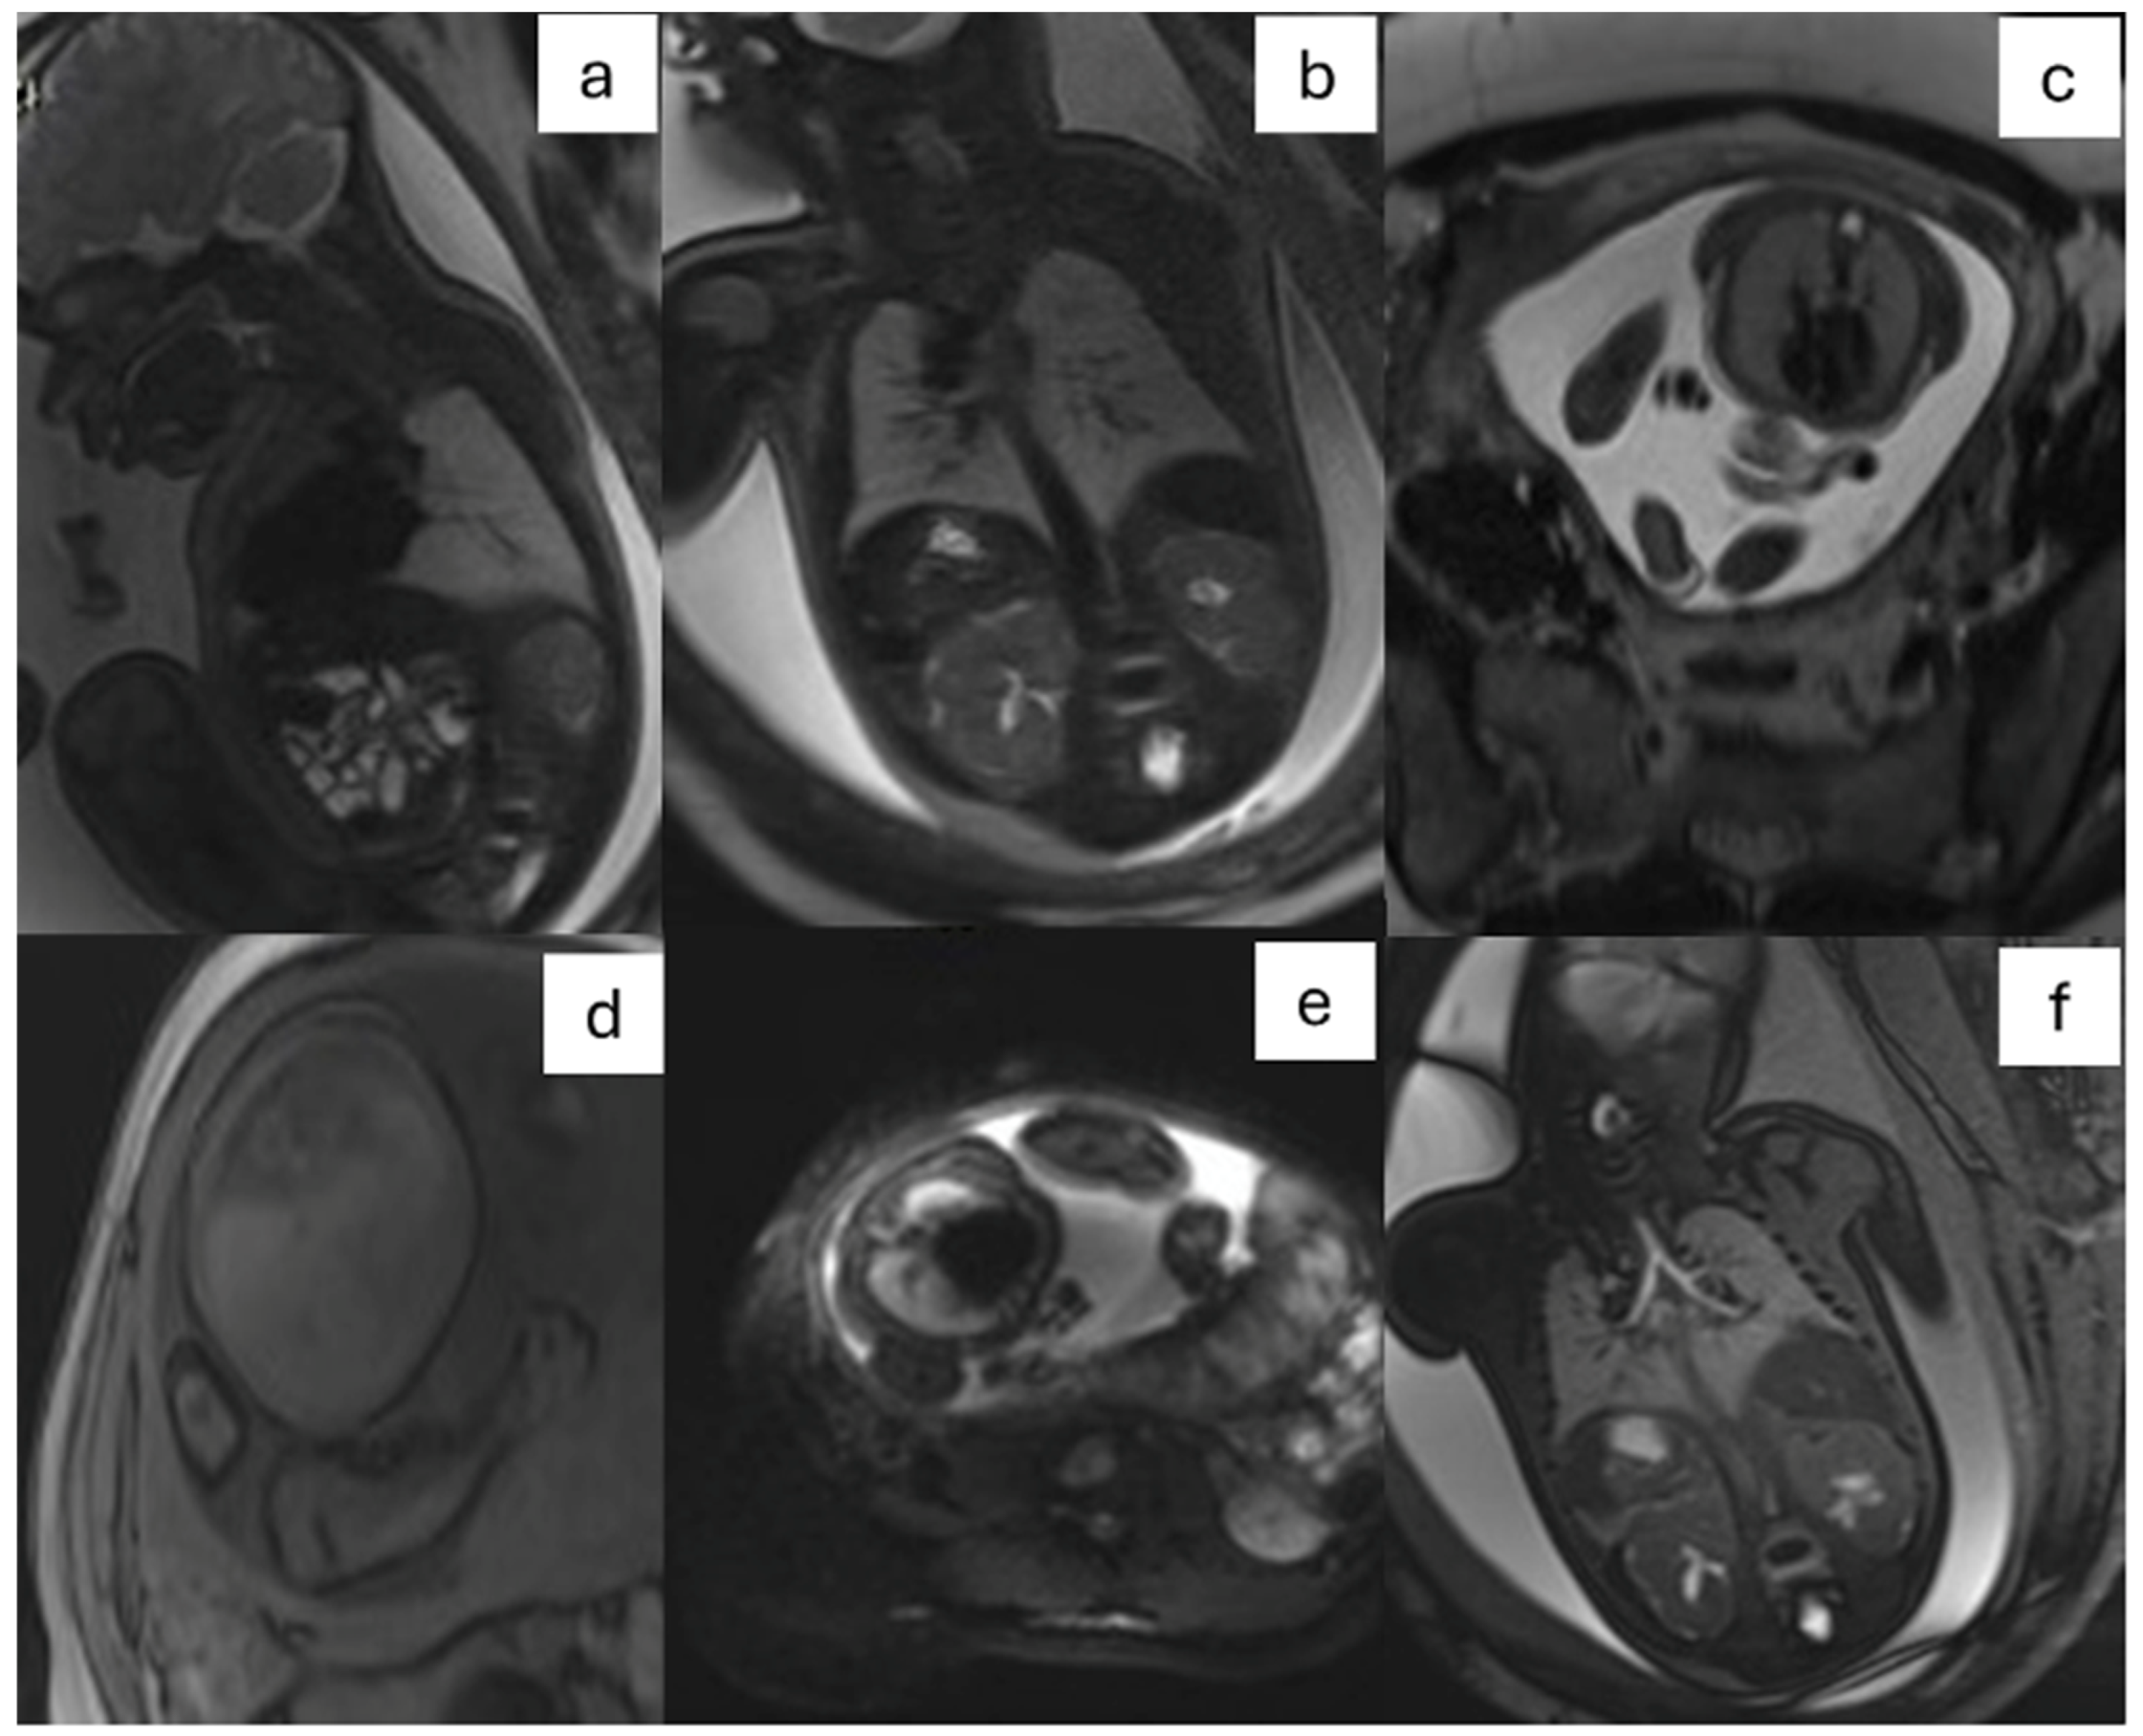

- CPAM: This is the most frequent malformation, consisting of communication with the normal tracheobronchial tree. They can present in solid or cystic form and are classified into 5 subcategories (Figure 2).